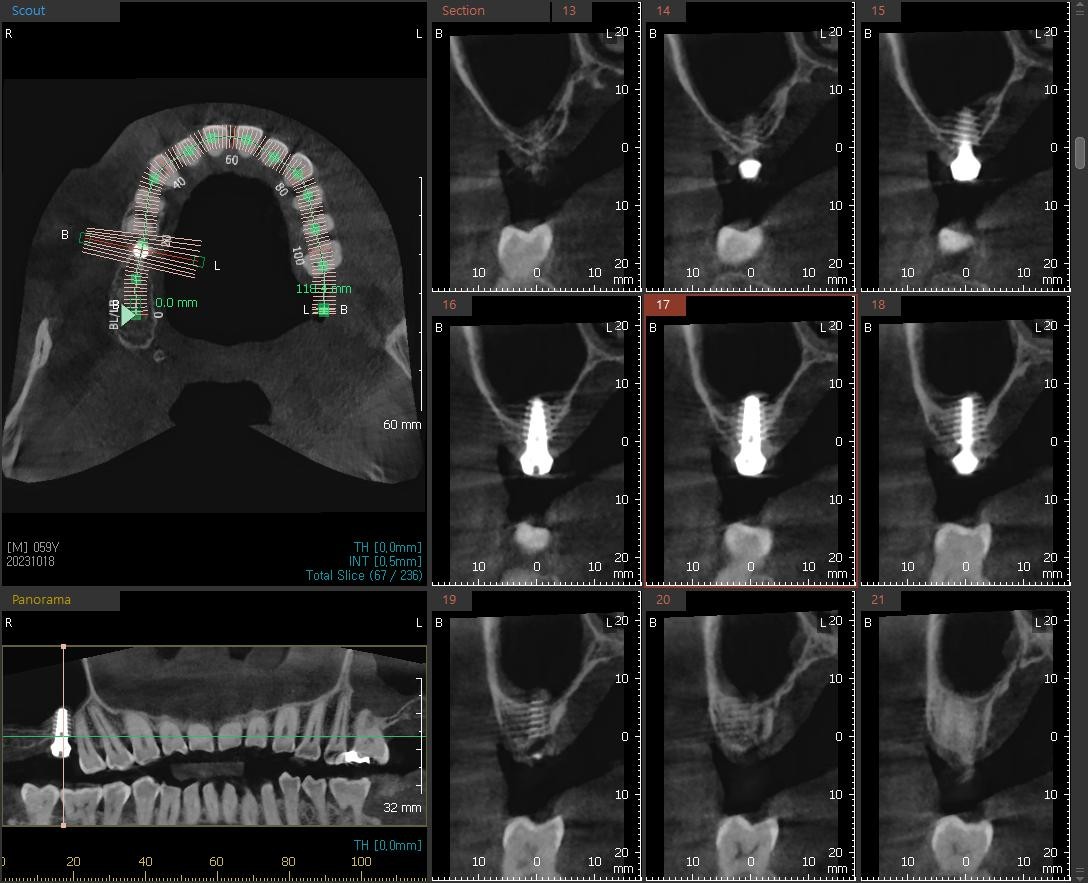

½Ä¸³ÈÄ ÆÄ³ë¶ó¸¶ »çÁøÀÔ´Ï´Ù.»ó¾Çµ¿ °Å»óÀ» ÁøÇà ÇßÀ¾´Ï´Ù.À̰͵µ ÀÕ¸ö Àý°³¸¦ ÇÏÁö ¾Ê°í »ó¾Çµ¿ ¸·À» °Å»óÇѰæ¿ìÀÔ´Ï´Ù.

ÀÌ°Ô ¹Ù·Î ¿äÁò ÀúÈñ º´¿ø¿¡¼ ¸¹ÀÌ ÇÏ´Â ÃÖ¼Ò Ä§½À ÀÓÇöõÆ®ÀÔ´Ï´Ù.